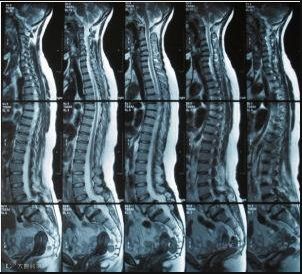

让腰椎重回26°,干嘛都不累

平躺或侧躺腰都不舒服

是因为正常腰椎是有曲度的

躺着时若没有东西垫着

腰椎会成为受力点

长期重力压迫到腰椎神经

想想就可怕

与海外医科大学联合

经过上百次测试

采用3D数字化技术精准建模

腰椎与枕26°紧密贴合

从人出发,符合人体构造